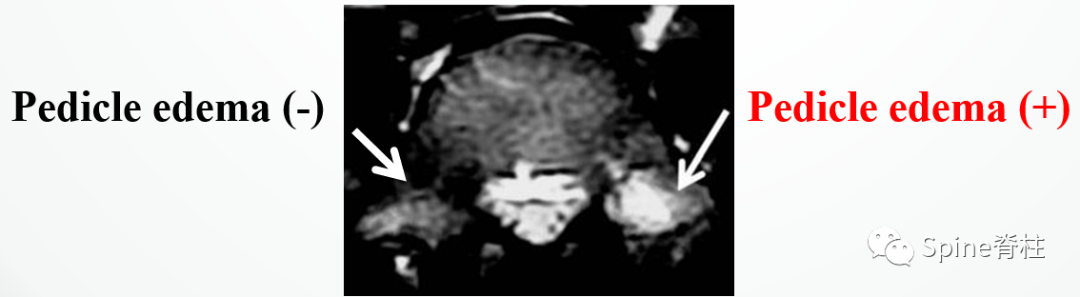

腰椎的解剖和峡部位置。从侧位(i)向右逐渐旋转至正位(iv)观察。红色箭头处为峡部。a=椎体;b=椎间盘;c=椎弓根;d=横突;e=上关节突;f=下关节突;g=棘突;h=椎板。PMID: 30396669